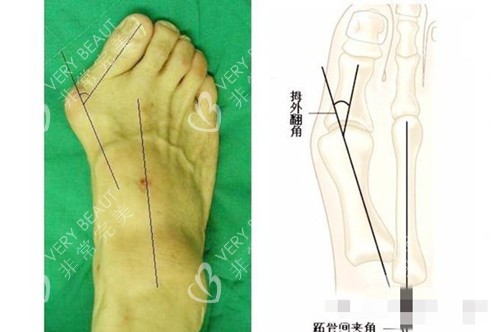

为了确认,我又跑了两家医院。一家说要切开5cm,术后得躺半个月;另一家医生说得打钢钉,我一听就怕了。直到见到圣嘉新的苏医生——他拿着我的X光片,用铅笔在脚上画标记:你这属于中度拇外翻,用小切口技术,不用钢钉,术后当天能下地。那语气特别稳,我一下就踏实了。

他操作时会轻声说:现在调整骨头位置、缝两针就好。我偷偷看了眼屏幕,原来小切口真的只有指甲盖大小!整个过程40多分钟,结束时苏医生举着镜子:你看,拇指已经直了,等消肿会更自然。我盯着镜子里的脚,眼眶突然有点热。